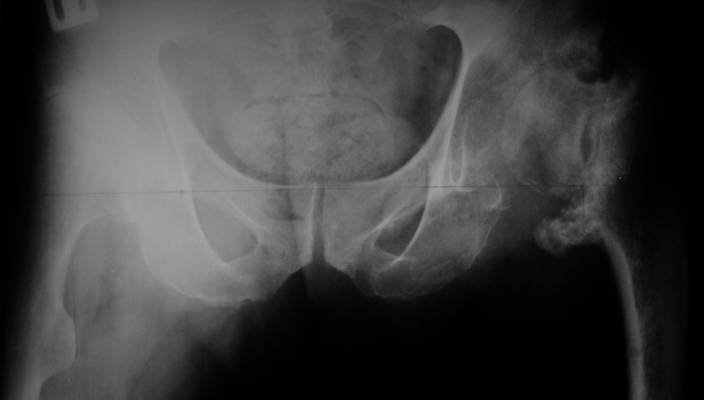

А за счет чего такое укорочение? По снимку не видно соответствующего дефекта. Ну плюс приводящая контрактура - но все равно как-то уж больно много. Может, сделать снимки и таза обзорный с обоими проксимальными отделами бедра, и коенный суставов с приложенной линейкой какой?

Судя по снимку, максимум истинное укорочение около 4 см, что может быть коррегировано интраоперационно. Вопрос в другом: куда ставить ацетабулярный компонент в истинную или во вновь сформированную ( впадина диспластичная).

Невозможно не согласиться с Анатолием, чтобы заниматься адекватным планированием как минимум прямая проекция таза должна быть сделана, как

максимум для оценки состояния мышц( насколько реально возможно низвести бедро) прямая проекция таза с тракцией за больную ногу.

The X ray that you provided does not show 8 cm of shortening. Perhaps you could send one showing the whole pelvis and proximal femurs.

I agree with Dr Eid's comments. The origin of the 8 cm leg length difference is a puzzle. Is this a clinical measurement? In that case contracture of the joint might affect the measurement. Can we see an AP pelvis to include both hip joints (including a calibration object with a known length) so that the difference in leg lengths that can be ascribed to the hip deformity and bony reabsorption can be measured. This sort of xray will help with templating for the TJR also. I would be very tempted to do a one stage procedure and accept some shortening. Shoe lifts should take care of a 3-4 cm difference.

До травмы проблем с ногой не было. Укорочения, болей и т.п. не отмечал. Сегодня перемерял укорочение - меньше 7 см намерять не

По уровню малых вертелов (с учетом рентгеновского увеличения) получается 5 см. Клинически ногу низвести путем тракции невозможно. Из движений - сгибание до 40*, остальные движения "символические".

Ортопедическое укорочение пострадавшей ноги может быть и 7, и 10 см. за счет контрактур в тазобедренном суставе, а вот истинное укорочение, судя по представленным рентгенограммам, вряд ли больше 4 см.